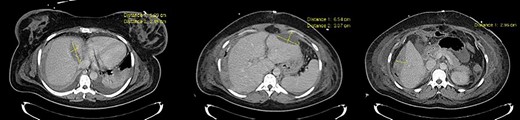

The postoperative period was favorable with lesion regression in serial Computed tomography scan control and was discharged on the 13th postoperative day (Fig. 2).